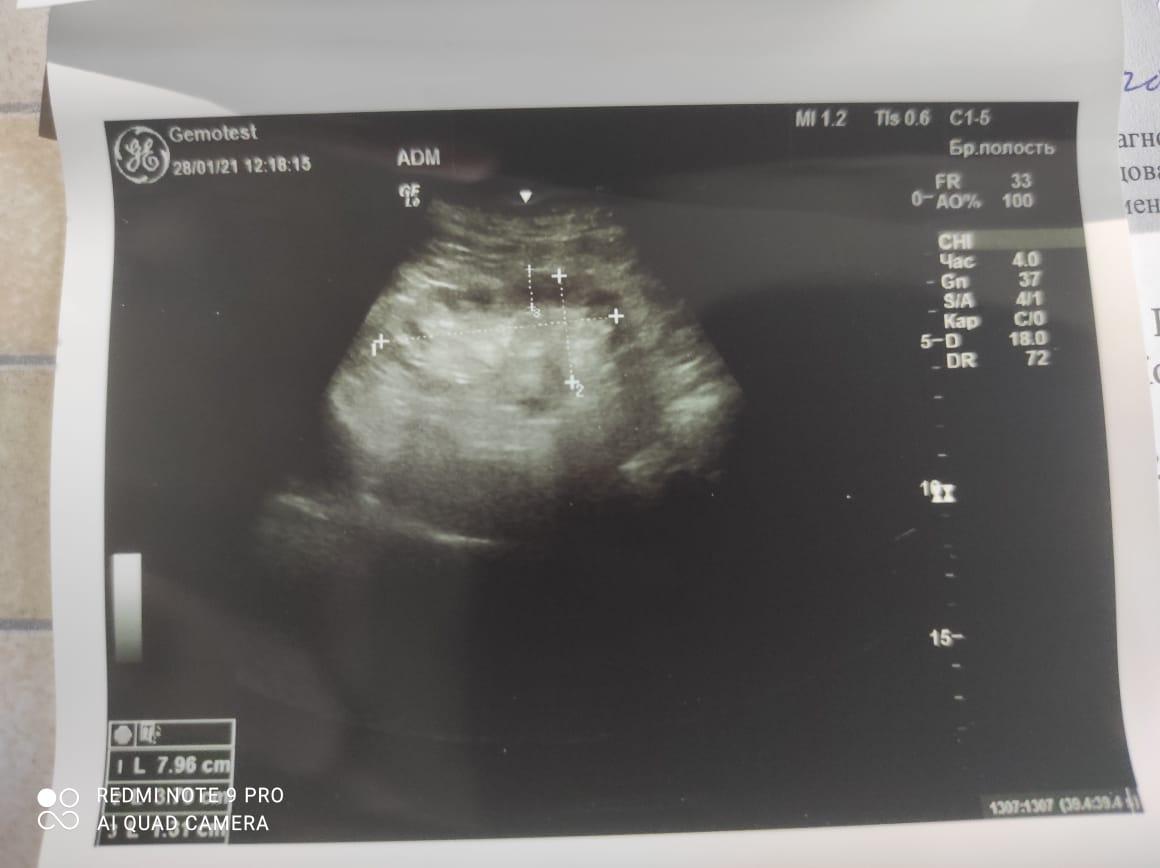

Здравствуйте! При наличии коралловидного камня правой почки(заключение УЗИ), можно предположить причиной боли нарушение уродинамики верхних мочевых путей), что, однако, не подтверждается результатами УЗИ почек( ЧЛС не расширена). Другая, наиболее вероятная возможная причина "боли в боку" - может быть патология опорнодвигательного аппарата. Необходимо проконсультироваться с неврологом и урологом очно, и согласовать возможность применения противовоспалительных, обезболивающих и спазмолитических препаратов - как первый шаг. В дальнейшем необходимо планировать возможное дальнейшее обследование и лечение. Удачи!